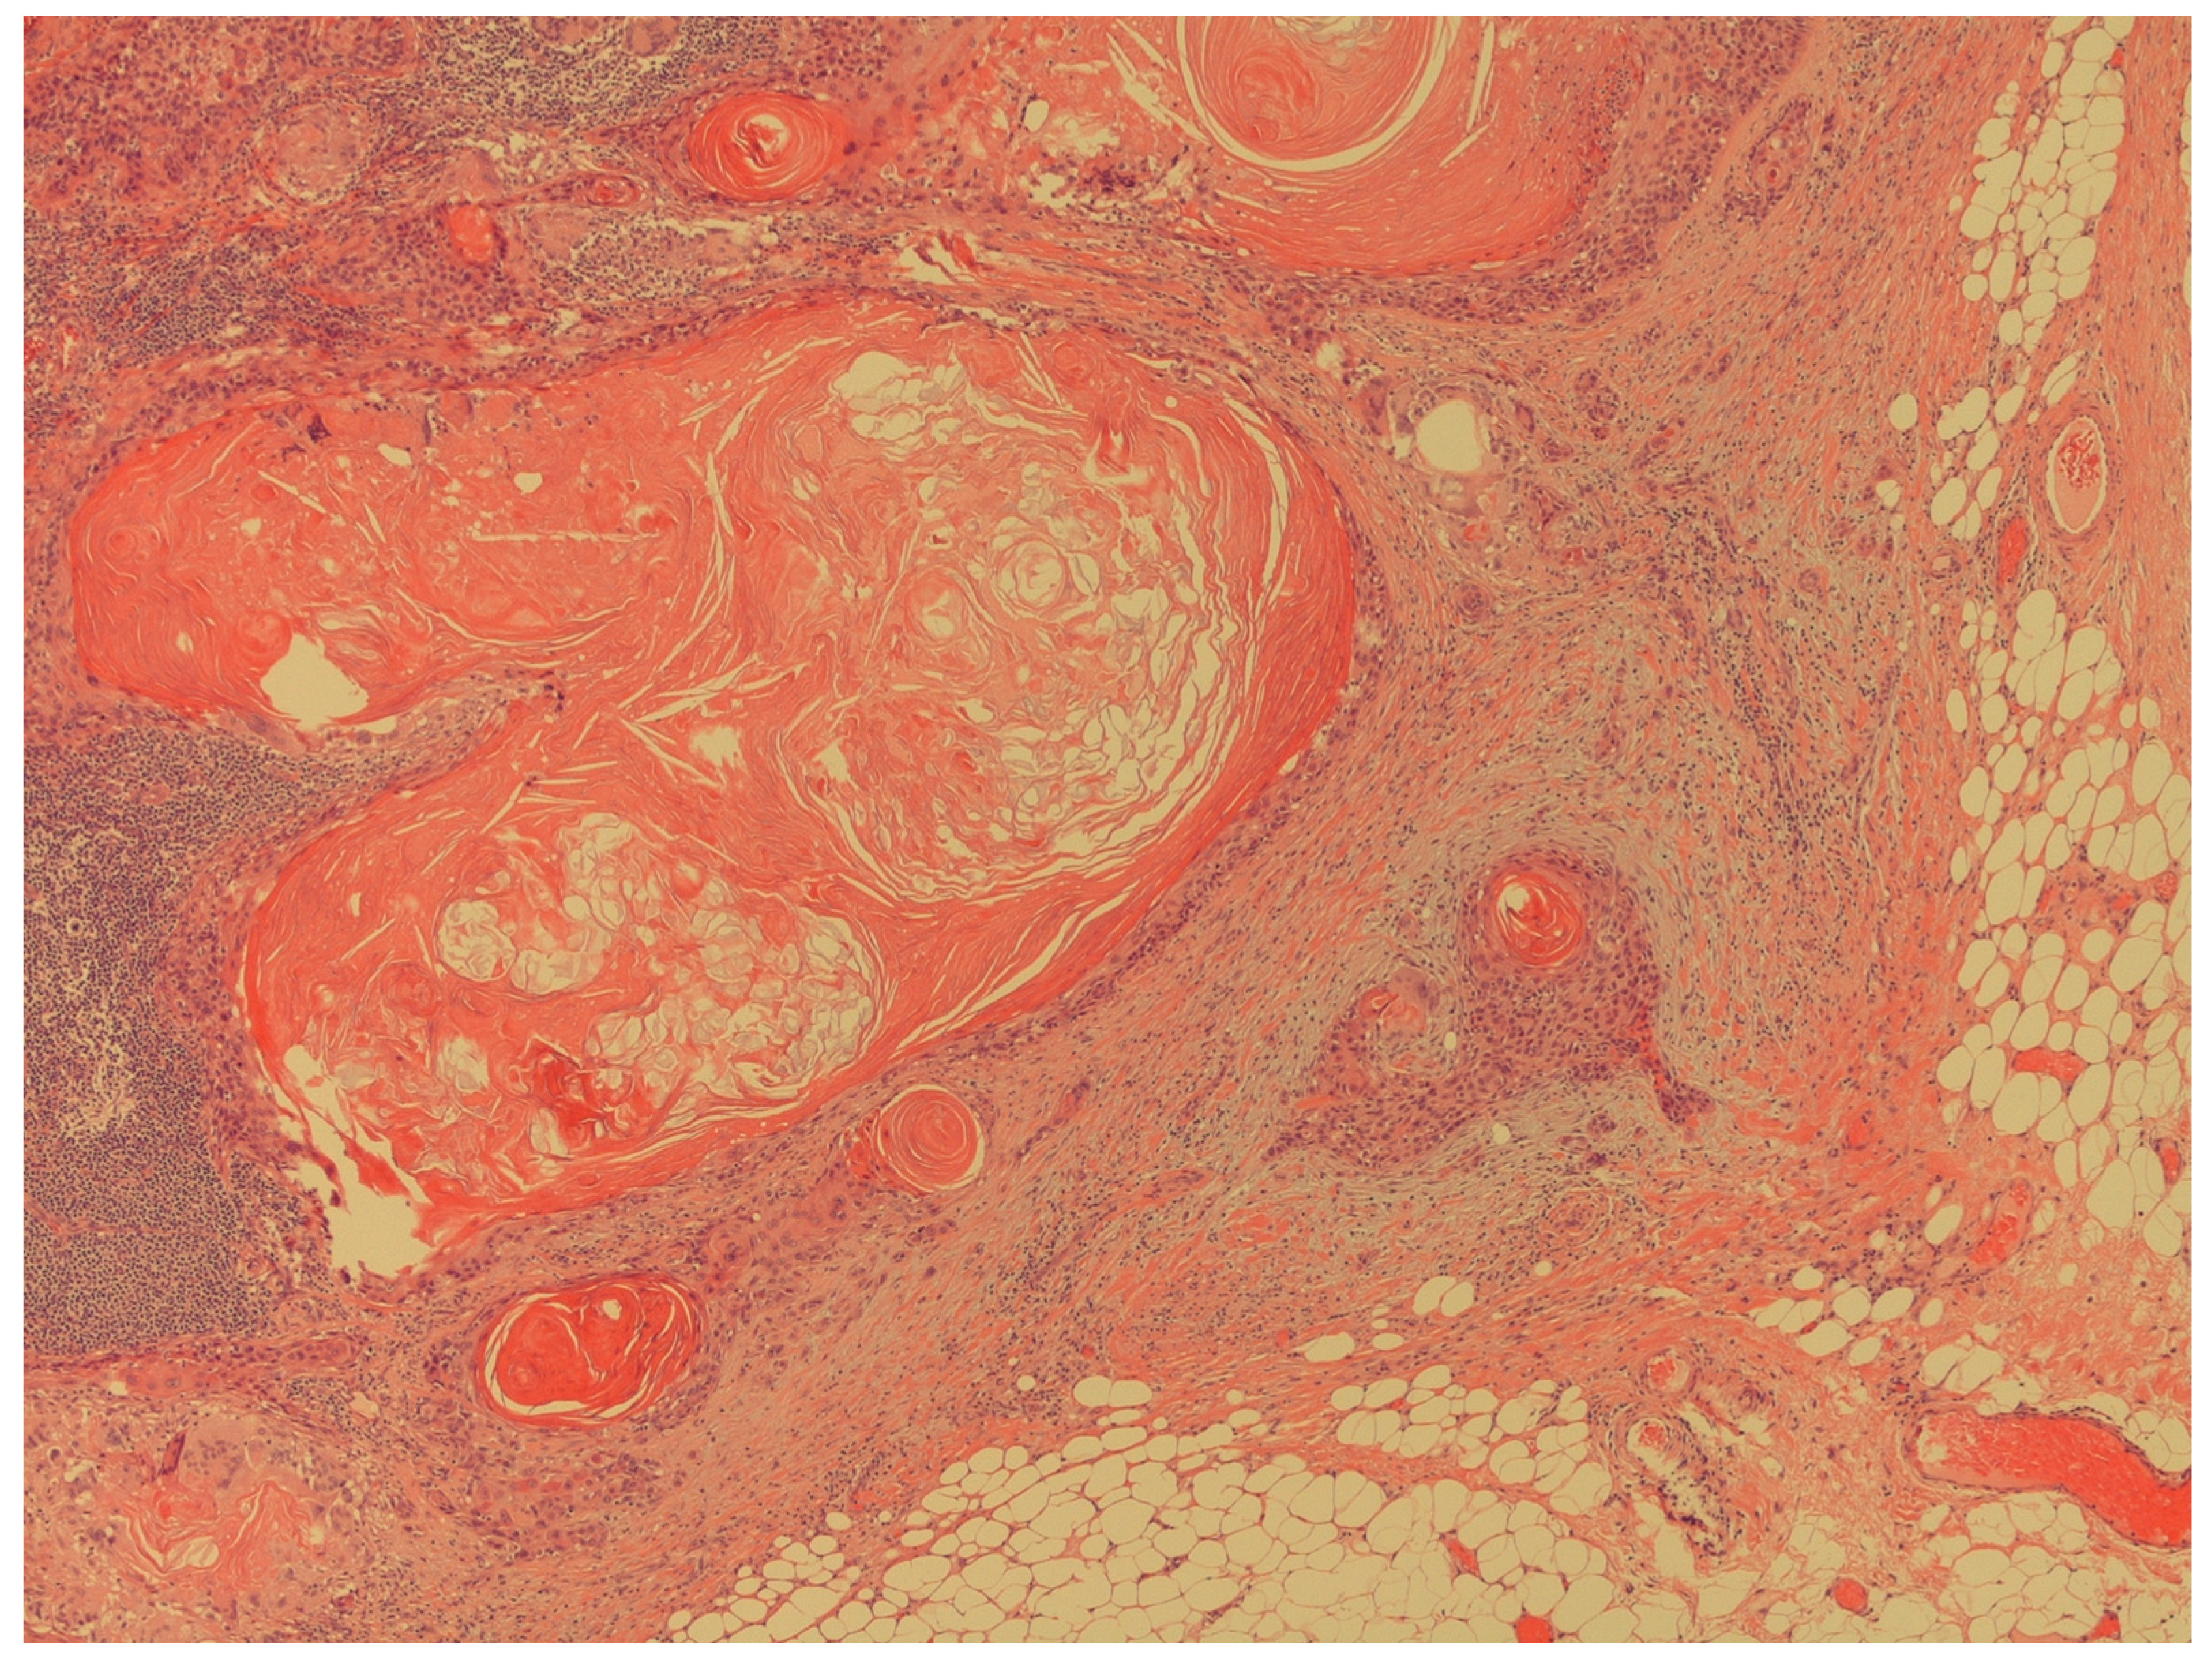

- Presence of extra nodal extension of cancer in lymph nodes (Figure 5).

Figure 5. The figure shows an extracapsular neoplastic extension from the foci of squamous cell carcinoma (H&E; 40X).